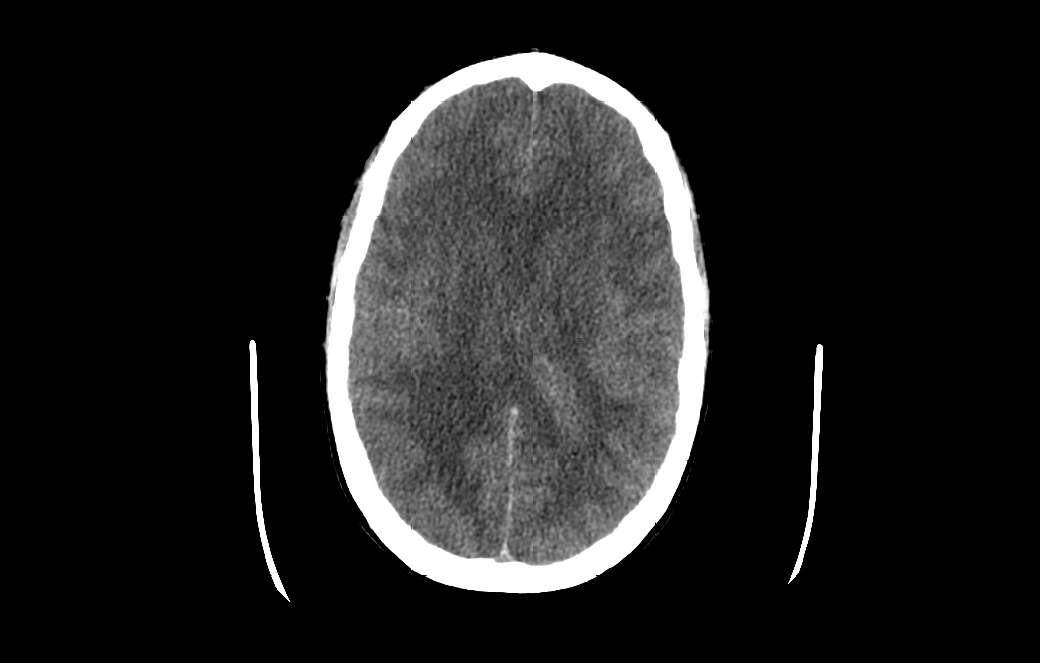

Case Presentation: 46-year-old female patient with a past medical history of ESRD on hemodialysis, DVT on chronic anticoagulation with apixaban, chronic HFrEF and history of injectable drug use (fentanyl) who presented with a chief complaints of progressive headache followed by rapidly progressive confusion requiring intubation for airway protection. Diagnostic lumbar puncture was considered however deferred given apixaban coagulopathy and thrombocytopenia. Empirical broad-spectrum antibiotic therapy along with acyclovir was initiated for suspicion of meningitis/encephalitis. CT head within 12 hours of presentation suggested evolving cerebral edema and CT angiogram of the head revealed diminished anterior intracranial circulation. Patient was treated with hypertonic saline. MRI of the brain revealed diffuse global cerebral and cerebellar diffusion restriction without diffuse enhancement (suggesting against an infectious etiology) likely consistent with opiate drug abuse. EEG ruled out nonconvulsive status epilepticus. Clinical course and presentation was highly suspicious for fentanyl induced leukoencephalopathy which can cause diffuse cerebral edema. Hospital course was complicated by hemodynamic instability requiring multiple vasopressor support and despite aggressive medical therapy, the patient continued to deteriorate clinically. Follow-up CT revealed catastrophic cerebral edema with complete effacement of all ventricles and sulci with evidence of transtentorial herniation. NM brain scan SPECT demonstrated an absence of cerebral perfusion. Serial brain death examinations demonstrated absence of all brainstem reflexes and cortical function without any confounding conditions and brain death was eventually declared.

Discussion: Opiate induced toxic leukoencephalopathy (TLE) is a rare and life-threatening complication of fentanyl overdose which is frequently under-recognized. Pathophysiology involves damage of brain white matter with myelin sheath injury. Clinical manifestations range from mild confusion to stupor, coma, and death. Prognosis depends upon the degree of damage. Differentials including hypoxic, ischemic, vascular, metabolic and infectious causes should be ruled out by comprehensive clinical evaluation, imaging, and lab testing (LP, EEG). Management is usually supportive, focusing on controlling intracranial pressure to avoid neurological complications with limited role of hyperosmolar therapies and corticosteroids. Severe cases may require intubation for airway protection and emergency neurosurgical intervention.